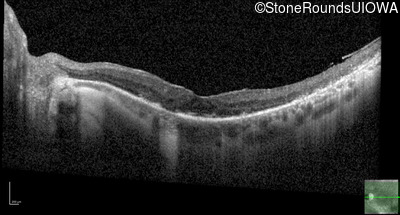

Optical Coherence Tomography - Left - 20/25 sc

Exemplar / OCT Stack

OCT Stack